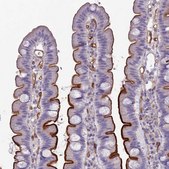

immunohistochemistry: 1:200-1:500

The Human Protein Atlas project can be subdivided into three efforts: Human Tissue Atlas, Cancer Atlas, and Human Cell Atlas. The antibodies that have been generated in support of the Tissue and Cancer Atlas projects have been tested by immunohistochemistry against hundreds of normal and disease tissues and through the recent efforts of the Human Cell Atlas project, many have been characterized by immunofluorescence to map the human proteome not only at the tissue level but now at the subcellular level. These images and the collection of this vast data set can be viewed on the Human Protein Atlas (HPA) site by clicking on the Image Gallery link. We also provide Prestige Antibodies® protocols and other useful information.

- IHC tissue array of 44 normal human tissues and 20 of the most common cancer type tissues.